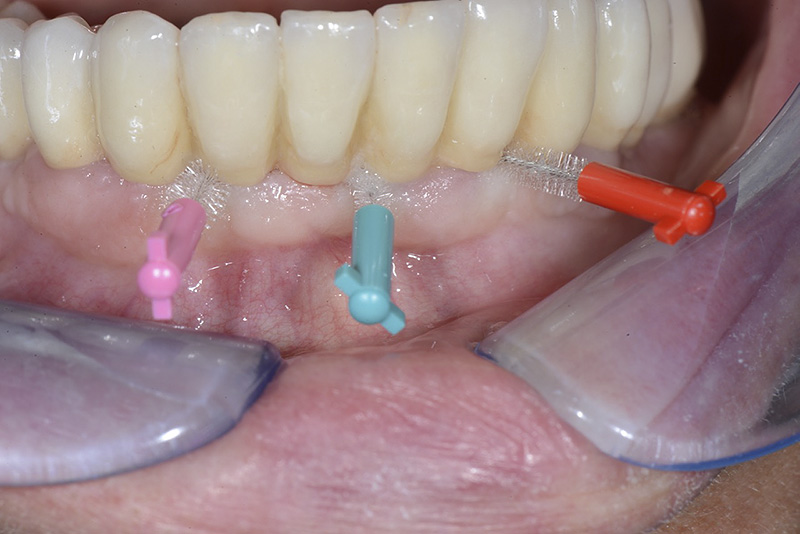

Vengono utilizzati 2 tipi di provvisori: il primo, cementato ai denti vicini, viene utilizzato dal momento dell’estrazione del dente fino ad impianto osteointegrato (circa 6 mesi); il secondo, avvitato direttamente all’impianto, ha una funzione di prova estetica ma soprattutto di guida per la maturazione dei tessuti gengivali peri-implantari portandoli verso la maturazione completa prima di posizionare la corona finale in disilicato di litio.